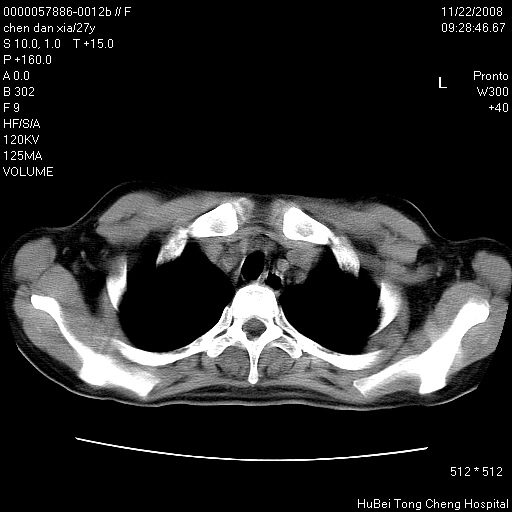

标题: CT16752:F,27Y。发热咳嗽20余天,伴盗汗。 [打印本页]

标题: CT16752:F,27Y。发热咳嗽20余天,伴盗汗。

建议强化观察,考虑肺门及纵隔淋巴结结核。另外还需结合实验室检查。

气管前腔静脉后淋巴结肿大 右肺门纹理模糊

淋巴结核?

右下肺纹理模糊;纵隔可见肿大淋巴节;右心缘旁结节,边缘光滑,纵隔窗病变范围较肺窗明显小,首先考虑右下肺结核,不排外淋巴瘤

下肺结节,结节内钙化,肺门纵隔淋巴肿大 结核可能性大

气管旁,两肺门可疑淋巴结肿大,建议ct增强.